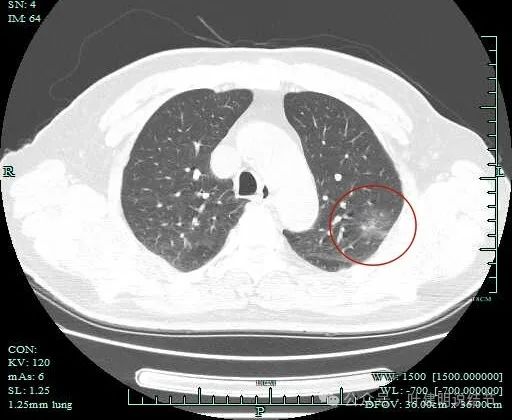

病灶出现,范围较大,密度较低,但轮廓较清楚。